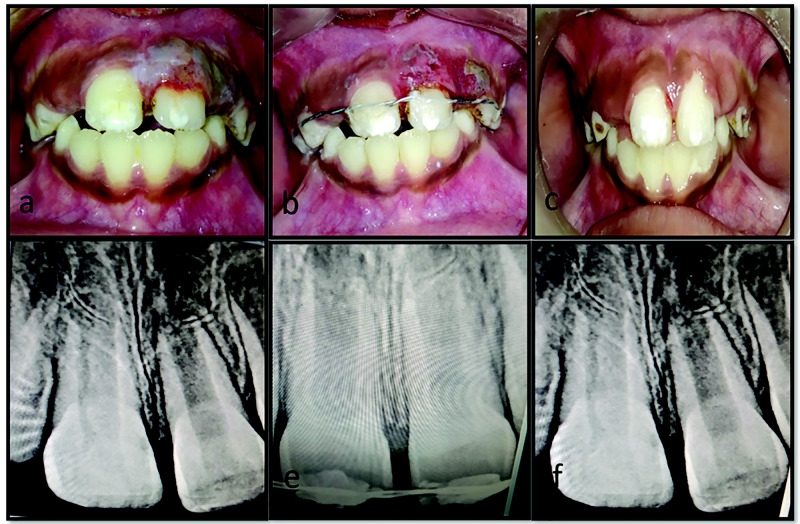

Dental injury is a common anesthesia-related adverse event, with a high incidence of damage to teeth and surrounding tissues during oro-endotracheal intubation. Poor oral hygiene, compromised periodontium, faulty or loose prosthesis, proclined maxillary incisors along with increased difficulty level of airway management, improper use of laryngoscope, and use of maxillary anterior teeth as a fulcrum for achieving accessibility to the airway are all risk factors for iatrogenic dental injury. This type of injury provides additional physical and psychological trauma to patients who have already undergone medical surgical procedures. The consequences of such mishaps might potentially result in medico-legal suits and financial claims. The present case series described three cases of managing iatrogenic dental lesions during oro-endotracheal intubation, after obtaining written informed consent, as well as methods for preventing such accidental injuries. This study emphasized the importance of collaboration between medical and dental professionals in preventing and successfully managing accidental dental injuries.